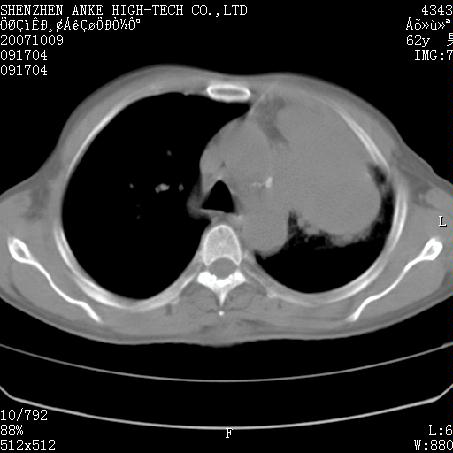

标题: CT9995:男,62岁,会诊,胸部平扫 [打印本页]

患者:男,62岁,咳嗽、胸痛、咯血约2月

左侧中央型肺癌伴上叶肺不张\\阻塞性肺炎.

左侧中央型肺癌伴上叶肺不张、阻塞性肺炎、纵隔淋巴结转移。支持!

左侧中央型肺癌伴上叶肺不张及阻塞性肺炎,纵隔内淋巴结转移